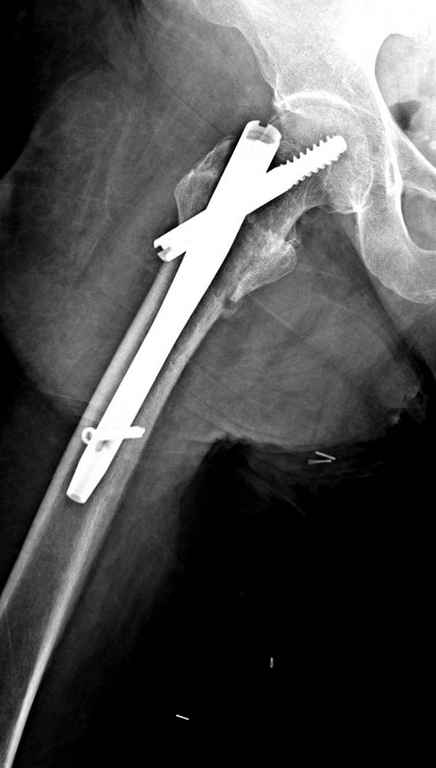

Перелом тут больше подвертельный. Нагрузка без торцевого упора на уровне перелома привела к телескопированию отломков на стержне. Ну и варус небольшой тоже свою лепту внес - если бы его не было, контактирующие латеральные стенки обоих отломков предотвратили бы укорочение, да и срослось бы за пару месяцев. А раз не срослось, упора отломков нет, более слабым местом оказались не нижние винты, а кость в головке и шейке. Так что надо было хотя бы удалить нижние винты до начала полной нагрузки.

Наверно, эндопротезирование. Есть более щадящий вариант - реостеосинтез (с устранением варуса и укорочения!), а после сращения и при наличии выраженного болевого синдрома - стандартное протезирование.